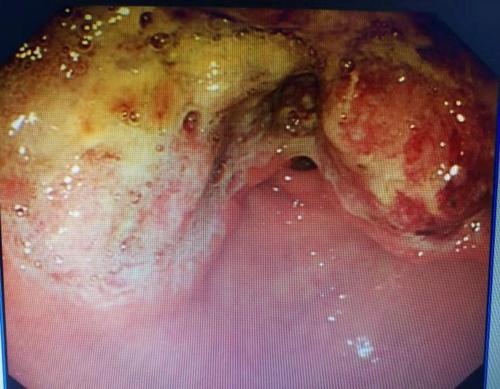

第三天 , 胃镜结果出来了 。

胃镜结果:胃巨大溃疡 , 胃癌可疑 。